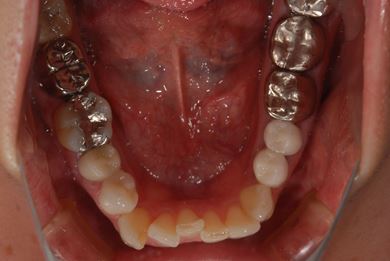

| 治療方針 | 上前歯部分、セラミック治療にて審美的回復を行う。 | ||||||||||||||||||||||||||||||||

| 治療内容 | オールセラミッククラウン3本(オールセラミック用土台3本)、メタルボンドセラミッククラウン1本 | ||||||||||||||||||||||||||||||||